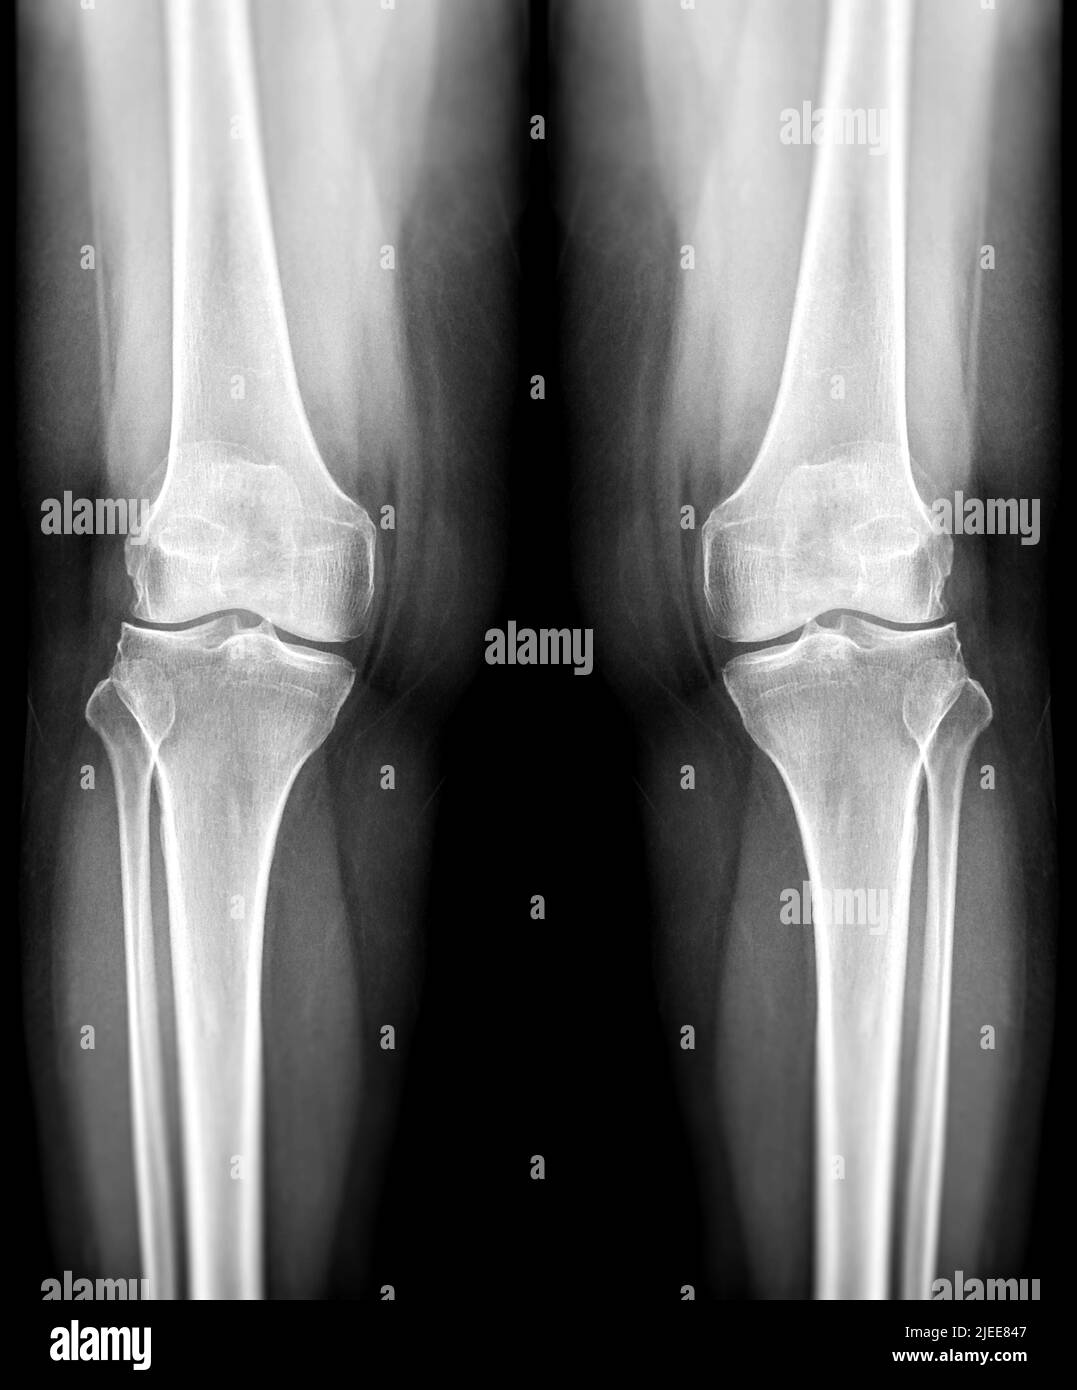

film xray both knee joint AP view for diagnosis knee pain from Floating Debris In Knee Joint loose bodies float around within the knee joint and cause pain, catching, locking, or swelling depending upon where the. They are tissues that have torn away from their. you may feel something floating in your knee joint because loose pieces of cartilage could be in there. a loose body is essentially a fragment of cartilage or bone. Floating Debris In Knee Joint.

Knee joint xray hires stock photography and images Alamy Floating Debris In Knee Joint loose bodies are another name for free floating pieces of debris in the joint. a loose body is essentially a fragment of cartilage or bone that has broken away from the surface of the knee joint. This has been ongoing since the end of. you may feel something floating in your knee joint because loose pieces of. Floating Debris In Knee Joint.